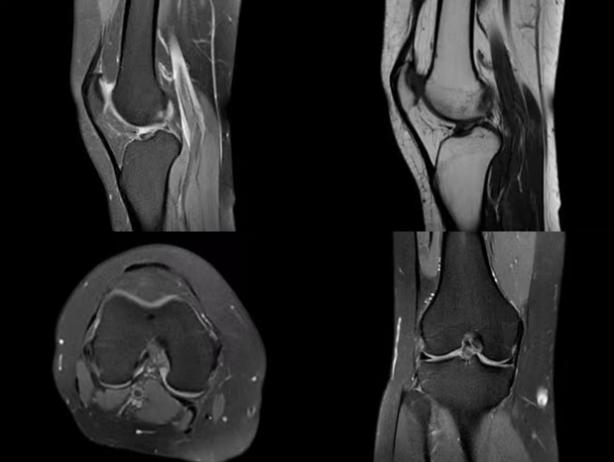

我们的服务项目涵盖了全身各部位的影像检查,包括但不限于:头部、颈部、胸部、腹部、盆腔、四肢等部位的CT、MRI、DR等检查。我们还提供特殊的影像检查服务,如血管造影、MR多功能成像等。例如:

磁共振检查: